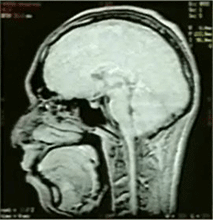

<口腔内のキーパーのMRI画像への影響>

キーパー部近傍(5cm未満)のMRI診断は困難になります。このキーパー部近傍の診断が必要な場合、MRI診断を行う医師よりキーパーの撤去を要求されることがありますので、患者への充分な説明を行ってください。

キーパーなし キーパーあり